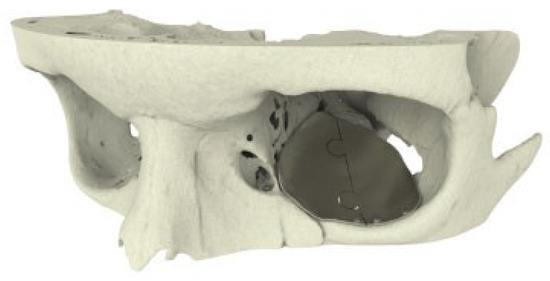

A 28-year-old man was referred with disabling diplopia and severe globe malposition after two repairs of an impure orbital floor fracture using a stock titanium orbital mesh plate (►Figure 9). He had been hit by a pulley in a work accident. The presence of the previously inserted titanium mesh slightly hindered implant design because of the scatter effect on CT scan. Mirroring revealed a height difference of 7 mm between the unaffected side and the mesh on the affected side (►Figure 10, Figure 11 and Figure 12). The 3D model had to take into account the lower position of the orbital rim, and the screw position was based on the amount of remaining bone and positions of the mesh, infraorbital canal, and lacrimal system. The porous implants were printed with a double tongue-in-groove design (►Figure 1 and Figure 10). The puzzle-piece design allowed precise fit between the first and second implants (►Figure 12). Anterior flanges were not necessary as the shape of the reconstructed infraorbital rim provided anteroposterior guidance. Slight diplopia in extreme upward gaze and lagophthalmos remained because of previous fibrosis (►Figure 9).

Figure 12. Case 3: Intraoperative 3D imaging using the Pulsera fluoroscopy system. (a) 3D reconstruction and section plane indication. (b) Good fit of the two puzzle pieces (long yellow arrow). Malpositioned mesh (short blue arrow). (c) Good fit of the medial puzzle-piece (long yellow arrow). The titanium mesh was not prebent and was 7 mm too low at the posterior sigmoid bulge (short blue arrow). (d) Axial view of the titanium mesh. The two-piece puzzle implants are visible only where they overlap the infraorbital rim.